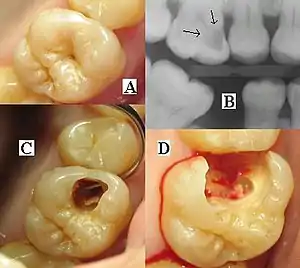

Dental radiographs, commonly known as X-rays, are radiographs used to diagnose hidden dental structures, malignant or benign masses, bone loss, and cavities.

A radiographic image is formed by a controlled burst of X-ray radiation which penetrates oral structures at different levels, depending on varying anatomical densities, before striking the film or sensor. Teeth appear lighter because less radiation penetrates them to reach the film. Dental caries, infections and other changes in the bone density, and the periodontal ligament, appear darker because X-rays readily penetrate these less dense structures. Dental restorations (fillings, crowns) may appear lighter or darker, depending on the density of the material.

It is possible for both tooth decay and periodontal disease to be missed during a clinical exam, and radiographic evaluation of the dental and periodontal tissues is a critical segment of the comprehensive oral examination. The photographic montage at right depicts a situation in which extensive decay had been overlooked by a number of dentists prior to radiographic evaluation.